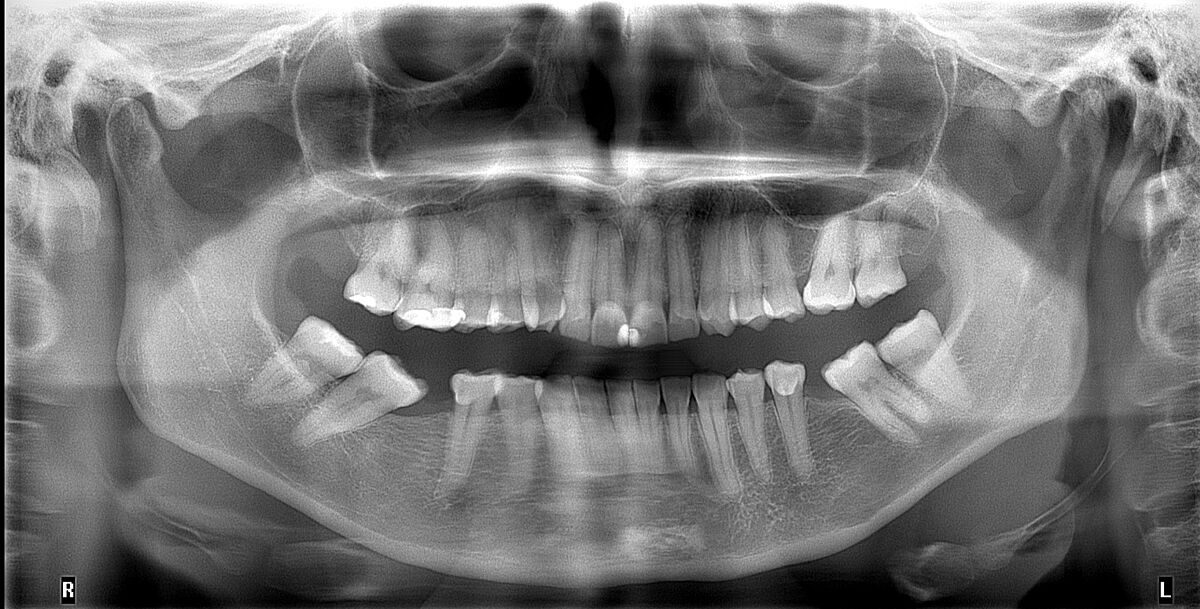

Как жевать, если нет 8ки и 6ки? И про импланты/мосты

У меня зубная диллема. Мне надо ставить брекеты на 2 года, чтоб раздвинуть 5 и 7 под импланты, внизу с обеих сторон нет шестерок. Ортодонт сказал, что с одной стороны не получится раздвинуть под имплант, только под мост. Но я же правильно понимаю, что мосты это ерунда и лучше имплант? Если под имплант, то говорит надо удалять восьмерки. Но как 2 года жевать одними нагнутыми семерками и пятерками? Это реально или плохая идея?

Ви що, не бачите, як ті вісімки вам зуби сусідні поздвигали? Їх треба було ще раніше поудаляти

8 теж здорові. Чому саме зараз вирішили щось робити? Що саме Вас турбує? Що з 5 зубами, там пломба є? Варіанти ще є, тільки у Вас, чомусь, найдорожчі.

Ви взагалі, чи саме про ці зуби? Ці зуби ’поздвигали’ відсутність 6, а не 8.

8 здорові, але зайві. Як найменш тому, що над ними не буде інших вісімок, а тому і жувальної функції не буде. Турбує що постирались зуби через неправильний прикус і продовжують стиратись, особливо з однієї сторони. Жування не повноцінне. + Планую в майбутньому відновлювати висоту, а без виправлення прикусу це не має сенсу. Напруження щелепи через стертий прикус. Пришвидшене старіння через це (поки що немає, але лікарі попереджують). Корочше причин вистачає

Ви вийшли заміж за ортодонта? Ваші 8 зуби в контакті. А де верхній 6 зуб? Як в майбутньому, запропонували підвищувати висоту прикусу?

8ки поки що в контакті, але після брекетів я так розумію вже не будуть. Я точно розумію, що я не хочу міст. Не знаю чому ортодонт каже, що не вийде посунути настільки, щоб імплант вмістився. Вверху 6й теж був видален, але підтягнулись і заповнили проміжок самі. Висоту піднімати вінірами

З Ваших слів Ви збираєтесь носити 2 роки брекети для того, щоб поставити 1 імплант? Чи доцільно це взагалі, якщо Ви не хочете міст, а по факту його отримаєте? Пошукайте ортодонта, який зробить так, щоб хоча б влізли імпланти.

Я планую брекети, щоб вирівняти прикус, поставити 2 імпланти і вініри. На міст я не згодна. Ну от як варіант видалити вісімки і тоді легше буде звільнити місця под імпланти. Не знаю, чи питання в ортодонті. Я закордоном і тут з цим питання не таке просте, але про цього ортодонта в мене найбільше інформації, ніж про інших і хоч відгуки є. Тому от і питаня, якщо знайти іншого, про якого нічого невідомо, який пообіцяє звільнити місце під імпланти, чи дійсно вийде і якщо і вийде, то чи не вийде це боком. Корочше непросте в мене рішення